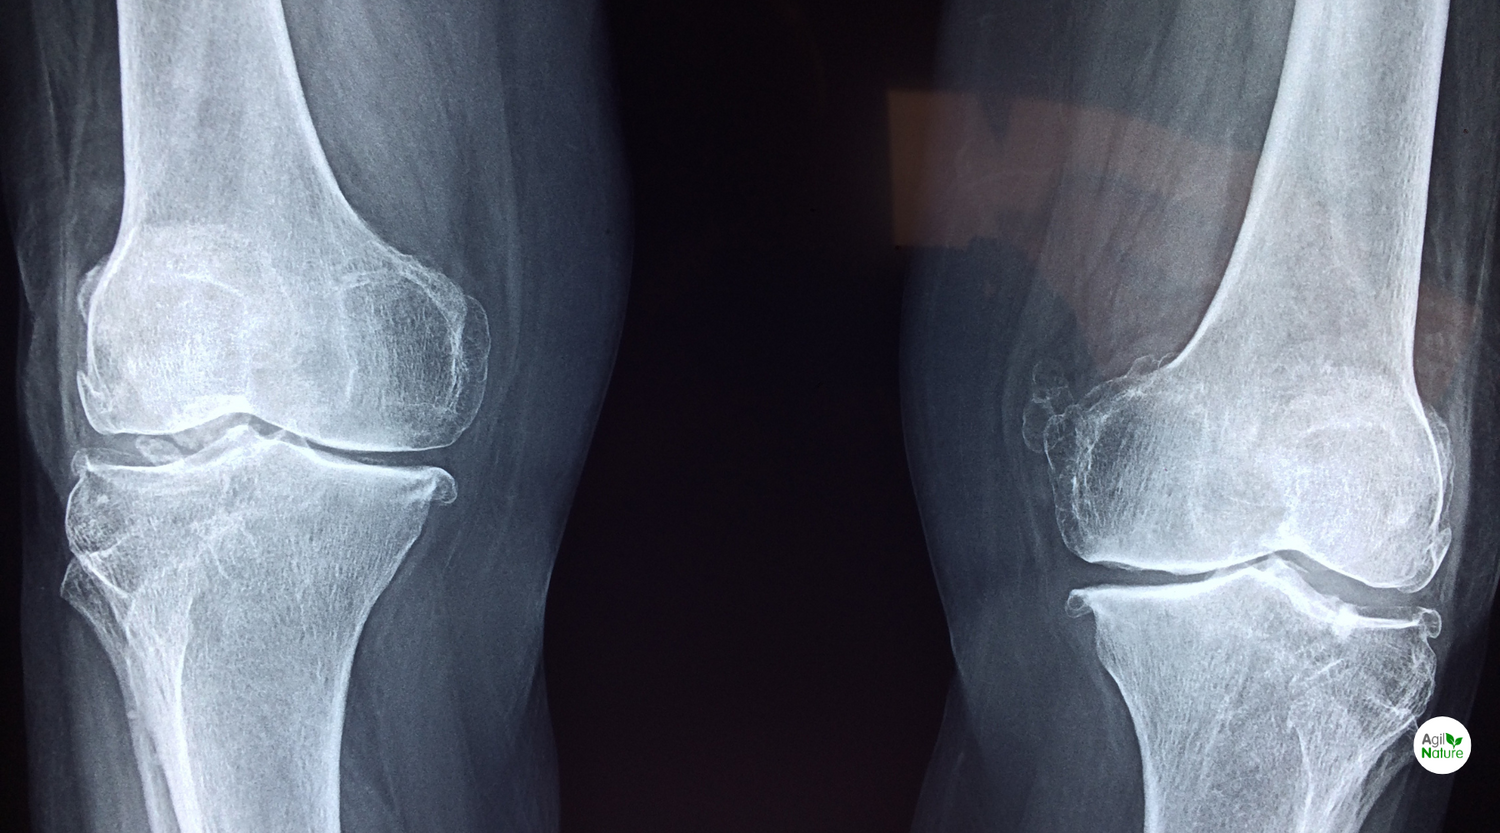

Das Wort Osteoporose steht für das Krankheitsbild des „porösen Knochens". Es stammt aus dem Griechischen: „Osteon" heißt Knochen, „Poros" ist die Pore. Bei Osteoporose verringert sich die Knochenmasse, was mit einer erhöhten Brüchigkeit einhergeht. Osteoporose tritt nicht wie lange Zeit fälschlicherweise behauptet nur bei Frauen nach den Wechseljahren auf. Auch Männer sind im höheren Lebensalter vom Knochenschwund betroffen. Jüngere Frauen sind immer häufiger von einer Knochenerweichung (Osteomalzie) betroffen.

Die Knochen stellt man sich gerne als starres, gewissermaßen lebloses Gewebe vor. Doch das Gegenteil ist der Fall. Unser Skelett ist wie eine Großbaustelle. Ständig wird Knochenmasse auf-, um- und abgebaut durch knochenaufbauende (Osteoblasten) und knochenabbauende Zellen (Osteoklasten). Innerhalb von 5 Jahren wird die Hälfte des Knochengewebes erneuert. (1) In der Kindheit und im Jungenalter überwiegt der Knochenaufbau. Im jungen und mittleren Erwachsenenalter liegt eine ausgeglichene Bilanz vor. Bis etwa zum 35. Lebensjahr ist die maximale Knochendichte erreicht. Je höher diese ausfällt, desto besser die Chance, auch im Alter von gesunden Knochen zu profitieren. Danach beginnt der Knochenabbau. Besonders bei Frauen nach den Wechseljahren kann der Knochenschwund dabei teilweise rapide verlaufen. Gerade eine Unterversorgung mit Calcium in jungen Jahren hat im Alter immer ein erhöhtes Risiko für Knochenabbau und für eine gesteigerte Knochenbrüchigkeit zur Folge. Der Verlust der Knochenmasse kann verhindert werden, da auch im Alter bei entsprechenden Maßnahmen die Knochenmasse erhalten werden kann. Zur Vorbeugung einer Osteoporose gibt es zwei Kernziele: in jungen Jahren die Knochenmasse optimal aufzubauen und im Alter den Knochenabbau möglichst gering zu halten (1).